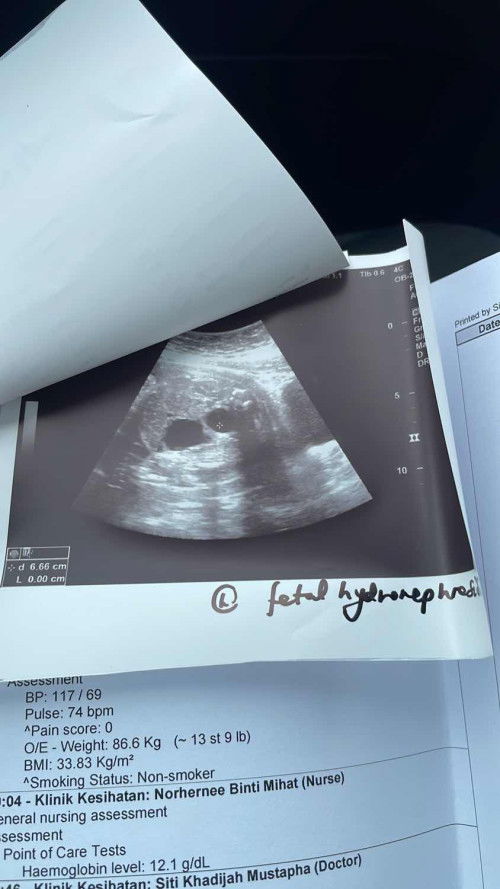

Hi assalamualaikum/salam sejahtera mommies. Dah disahkan oleh doktor setelah 3 kali scan my unborn baby ada masalah bengkak pada buah pinggang. Risau sangat sebab baby belum lahir dh ada penyakit 😢 appointment dengan doc pakar bulan depan. Ada sesiapa yg mengalami benda yg sama? Mind sharing? #pregnancy #AskingAsAMom #firsttimemom